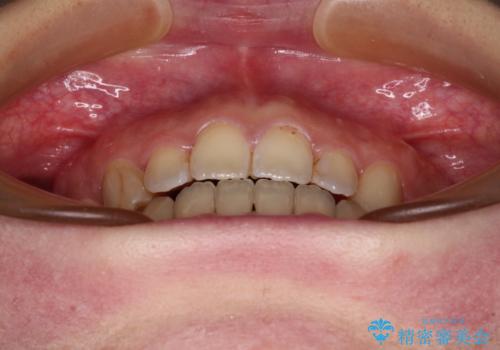

八重歯を抜歯矯正でスッキリと メタルブラケットでの矯正治療

- 八重歯と上下前歯のでこぼこを気にして来院された患者様です。

上下前歯部叢生のスペース獲得のため、上下顎左右小臼歯各1歯(計4本)と全ての親知らずを抜歯して、矯正治療を行うこととしました。

八重歯とは別に上下前歯の隙間という問題もありました。こちらは舌突出癖によるものと考えられたため、舌のトレーニングをしっかりと行っていただきました。